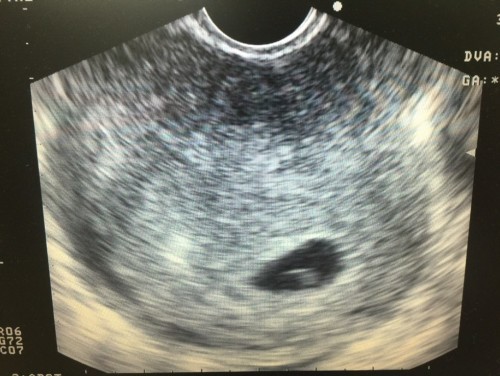

มีเลือดออกสีน้ำตาล เป็นอะไรไหมค่ะ เลยไปหาหมอหมอซาวดูให้ ตั้งครรภ์ประมาณ 5 W หมอบอกว่าน่าจะเป็นเลือดตกค้างแม่ๆคนไหนเลยเป็นบ้างไมค่ะ

เลือดออกเยอะมั้ยค่ะ ถ้านิดเดียว ออกตอน 5w เป็นสันยานการตั้งครรภ์ค่ะ เรียกเลือดล้างหน้าเด็ก เคยเป็นเหมือนกัน